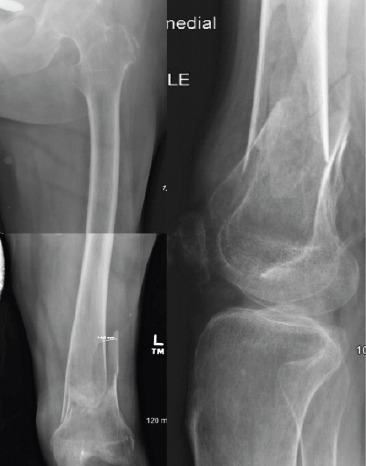

Case report: A 45-year-old male with T2 paraplegia presented with bilateral distal femoral shaft fractures following a motor vehicle accident. He underwent bilateral retrograde intramedullary nailing to preserve mobility and independence. Postoperatively, the patient developed a hypertrophic non-union on the right side with hardware migration, requiring revision with plate and screw fixation. Subsequently, he developed painful hardware on the right and severe heterotopic ossification on the left, significantly impacting his quality of life. Although hardware removal was recommended, the surgeries were never performed due to the patient's clinical course and eventual death from unrelated causes.